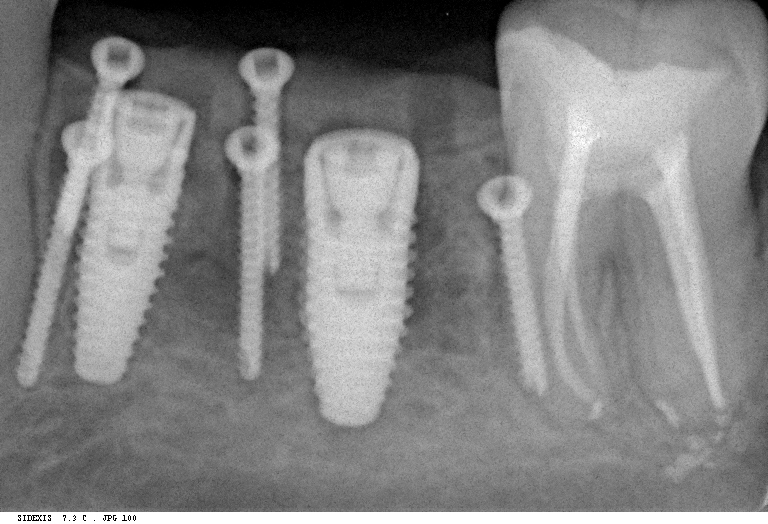

шмидт2   шмидт1

Снимок слева сделан сразу после операции, а справа — через 4 месяца, на этапе установки формирователей десны.